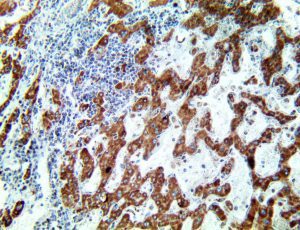

It is the ICU physician who is most likely to witness one of the deadliest manifestations of the abnormal immunological response, the cytokine storm syndrome (CSS). This response is also referred to by some as the cytokine release syndrome (CRS). CSS is characterized by continuous activation and expansion of macrophage and lymphocyte populations, which secrete large amounts of cytokines, causing the cytokine storm. This massive cytokine release is akin to hemophagocytic lymphohistiocytosis (HLH) disease, a syndrome characterized by initial unchecked and persistent activation of cytotoxic T lymphocytes and NK cells.

Clinical and laboratory manifestations of HLH include fever, enlarged liver and/or spleen, neurologic dysfunction, coagulopathy, liver dysfunction, cytopenias (i.e., low levels of erythrocytes, leukocytes, and/or platelets), hypertriglyceridemia, hyperferritinemia, hemophagocytosis, and eventually diminished NK cell activity as the immune system becomes progressively paralyzed. HLH can be familial (primary HLH) or secondary to another disease process (sHLH), such as rheumatic disease, in which it is referred to as macrophage activation syndrome (MAS, characterized by elevated ferritin).